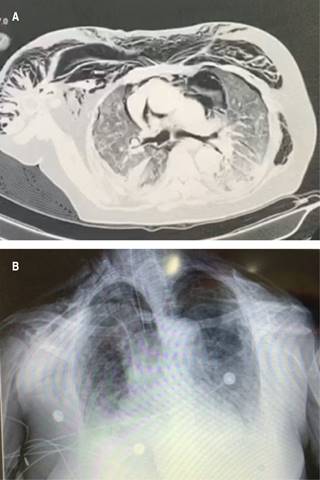

Figura 1: A) Tomografía de tórax, corte axial. B) Radiografía de tórax anteroposterior. Mujer de 66 años de edad, con diagnóstico de COVID-19 con RT-PCR+. En su séptimo día de estancia intrahospitalaria con ventilación mecánica invasiva presentó enfisema subcutáneo extenso a nivel cervical, supraclavicular y tórax anterior, así como neumomediastino.

Figura 2: Radiografía de tórax anteroposterior. Misma paciente con reducción importante de enfisema subcutáneo, mediante manejo conservador.